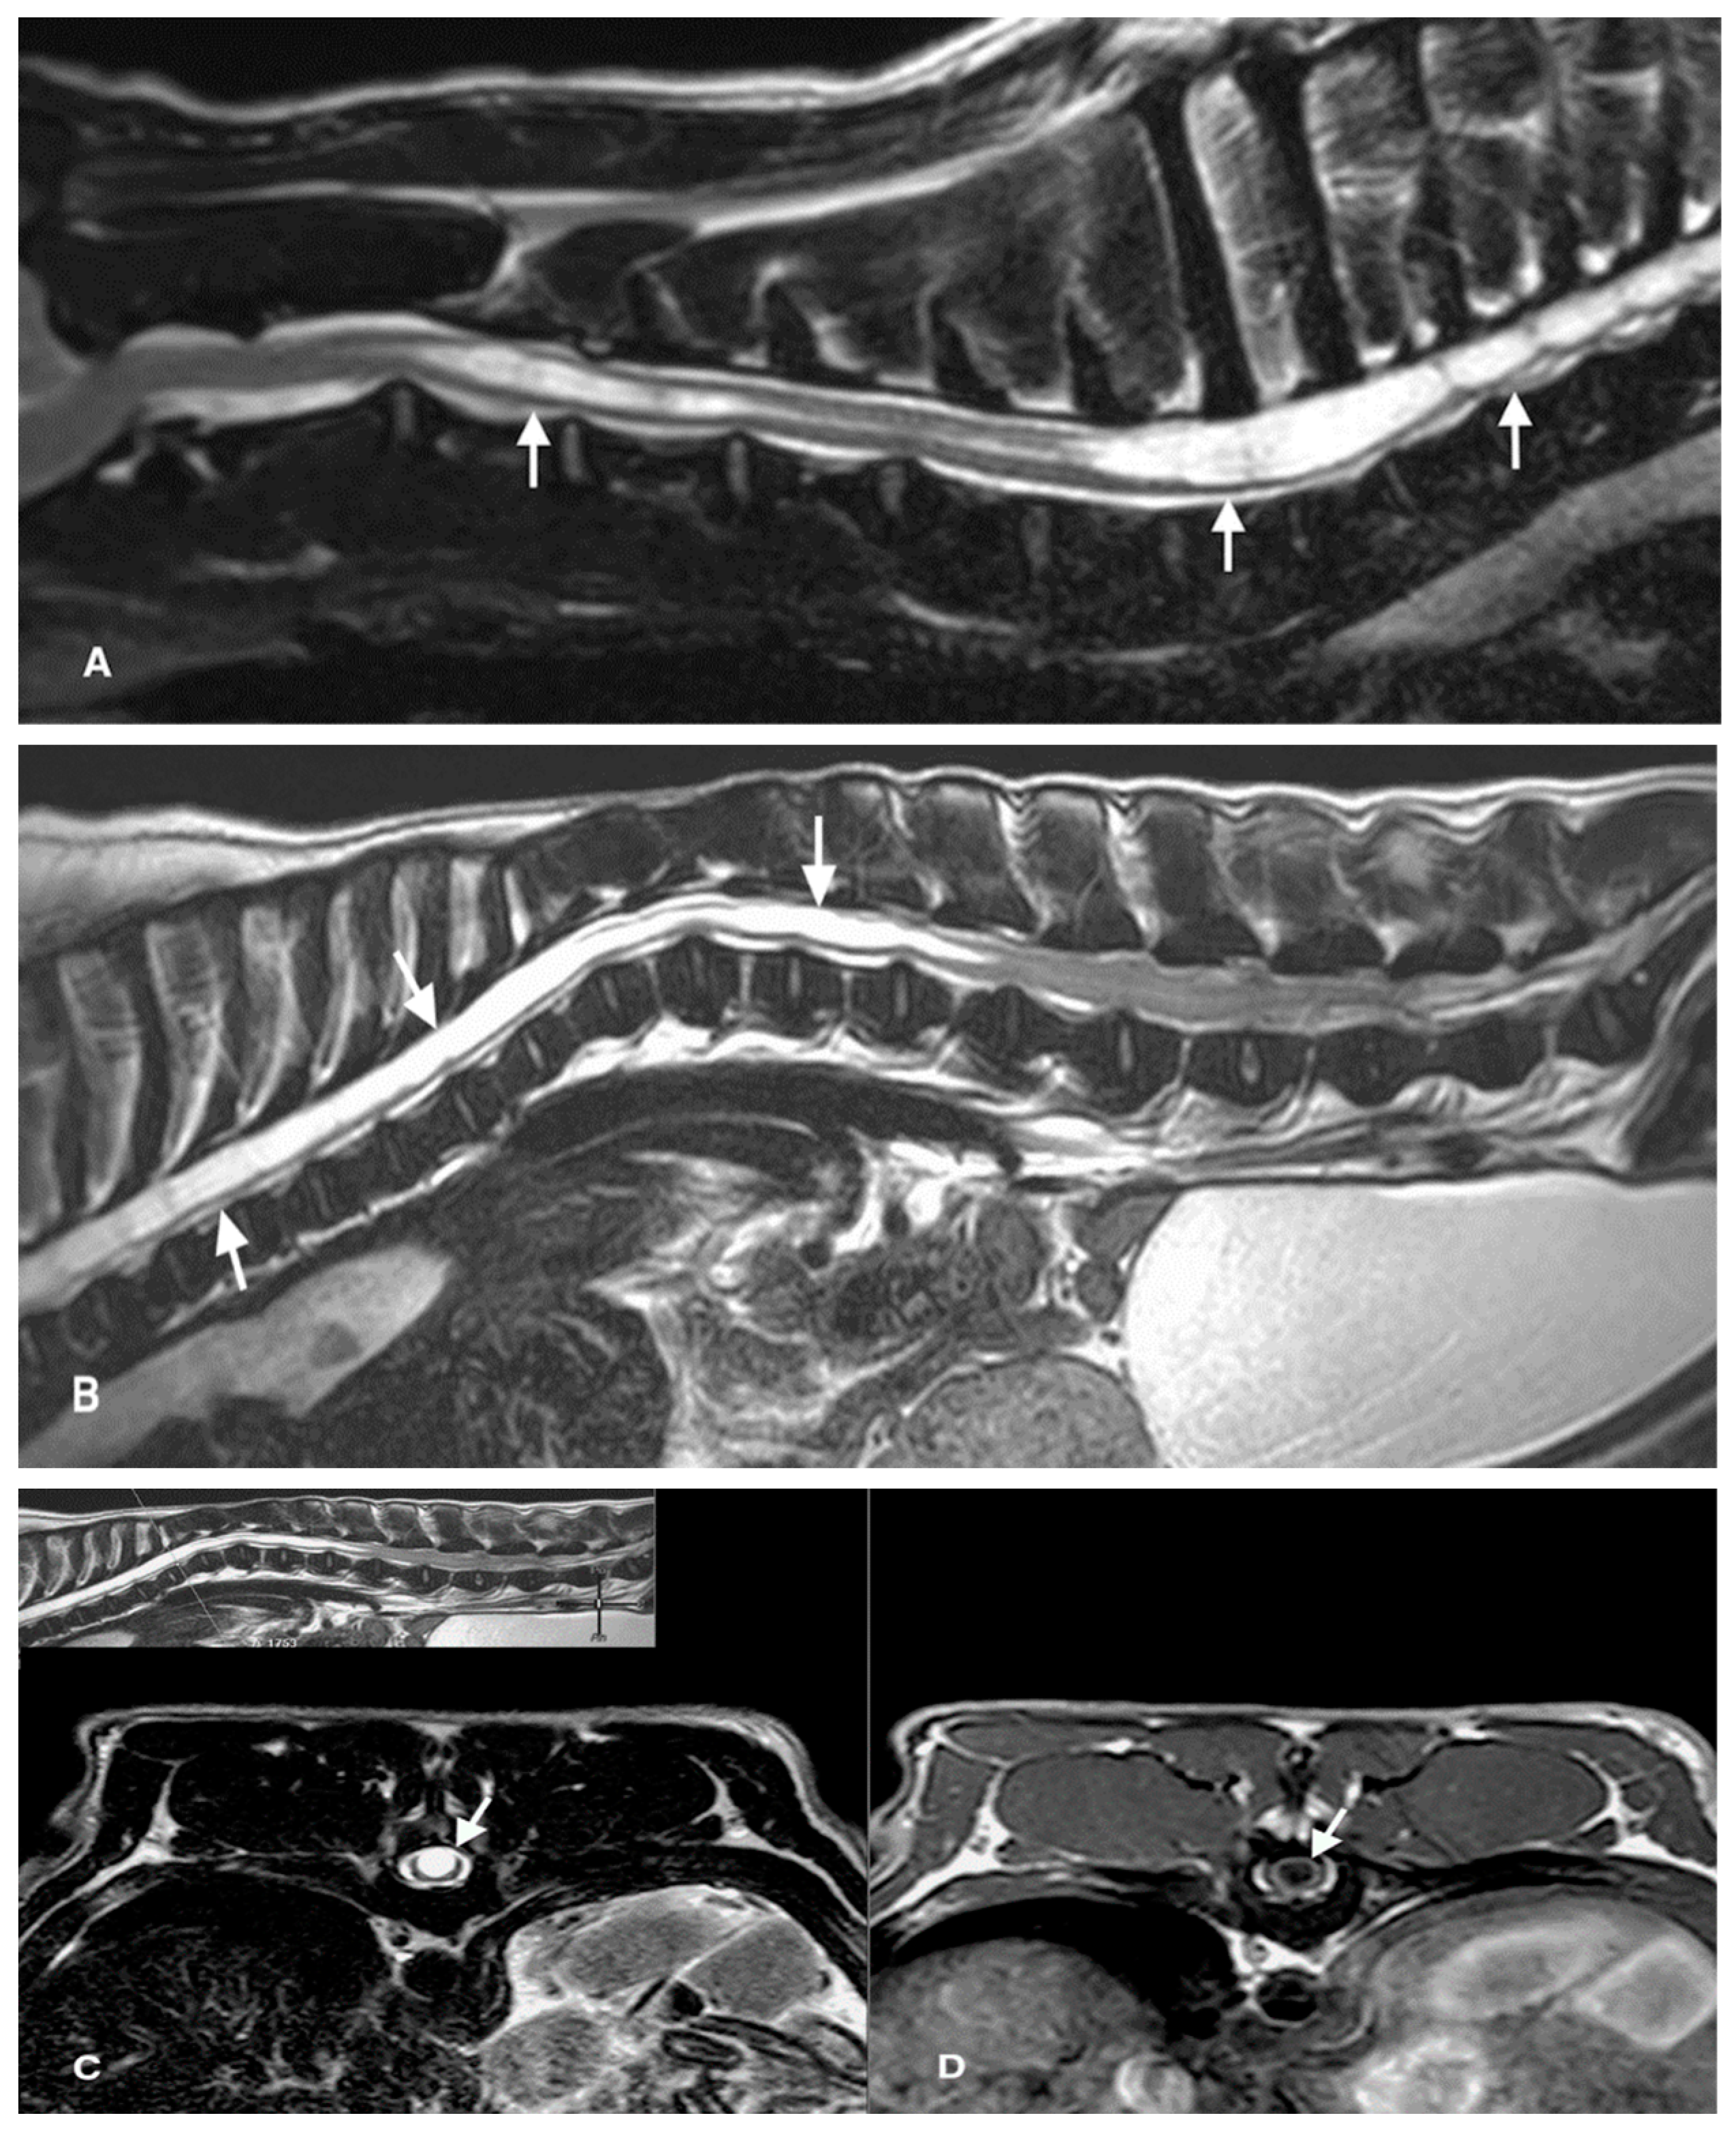

3. Results